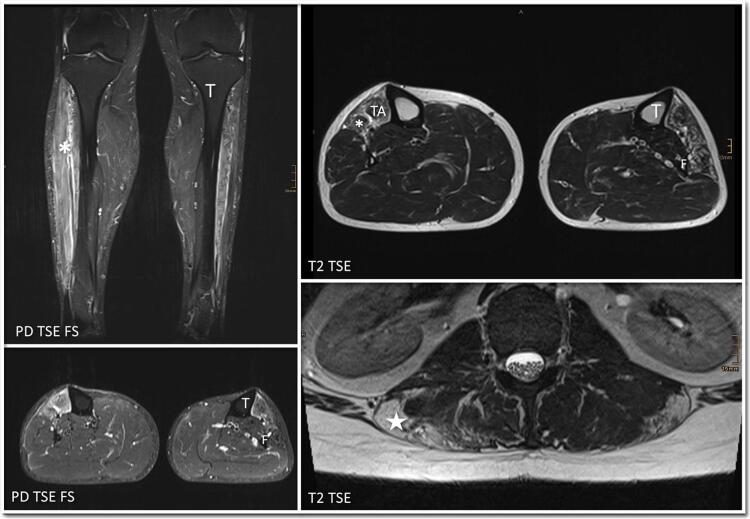

双侧足下垂为1型面肩肱肌营养不良的表现特征。

•FSHD1在成年期可能表现为双侧足下垂。•临床检查,肌电图和肌肉MRI可以额外指导基因检测。•有针对性的基因检测在非典型病例中至关重要,特别是考虑到新的治疗方法。

Bilateral foot drop as presenting feature of facioscapulohumeral muscular dystrophy type 1